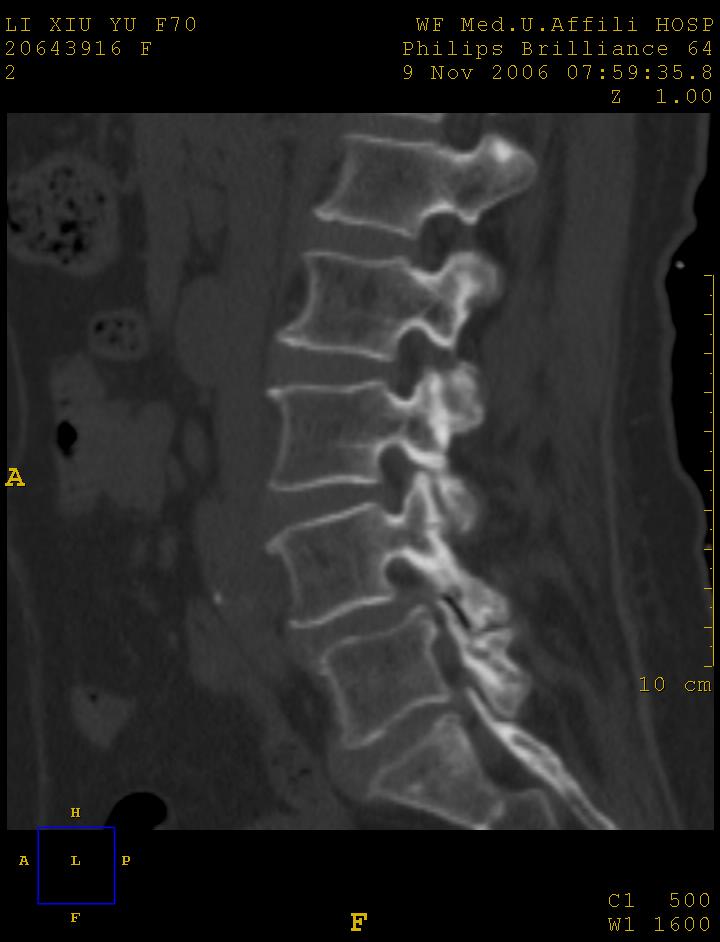

标题: CT5427:女,70岁,腰痛,清晰明了 [打印本页]

女,70岁,腰痛

l4椎体向前滑脱,椎弓裂

l3/4,l4/5,l5/s1椎间盘病变,l4以上向前ι度滑脱并椎小关节交锁、椎弓峡部断裂,椎小关节变性.

1:l4向前滑脱,l4-5小关节退性变。没有峡部裂。

1腰椎骨质增生,2l4向前滑脱(假性,矢状位椎弓峡部连续),3腰5-骶一椎间盘退变,4小关节面综合征

1 腰4椎弓崩裂,腰4椎体向前ι度滑脱并椎小关节交锁,腰4/5小关节明显增生硬化,间隙内可见真空征。

2 腰椎间盘不同程度膨出,腰4/5、腰5/骶1椎间盘突出,腰4/5椎间隙变窄,腰5/骶1间盘变性(间隙内可见真空征)。

3 诸椎体缘不同程度骨质增生,腰5、骶1后骨刺明显,腰5椎体后上缘可能有软骨结节(由于没有平扫,不易确定)。

诊断:腰椎退行性骨关节病。